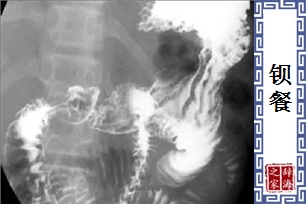

- 一种诊断某些食管、胃肠道疾患的检查方法。病人服硫酸钡后,用X射线透视或拍片检查有无病变。

【钡餐】 图片鉴赏